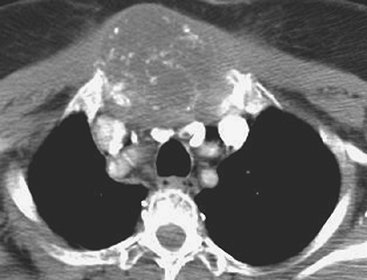

Malignant mesothelioma is a relatively rare primary tumor of the pleura. Approximately 80% of these lesions occur in individuals who have been exposed to asbestos (19). The lifetime risk for the development of mesothelioma in asbestos workers approaches 10%, and the average latency period is 35 years (20). Radiographic and CT findings include

P.148

nodular or irregular thickening of the visceral and parietal pleura, variable ipsilateral volume loss in the hemithorax, ipsilateral pleural effusion, involvement of the interlobar fissures and mediastinal pleural surfaces, and often fixation of the mediastinum (Figs. 9-18, 9-19, 9-20) (21). Approximately 18% of cases are associated with invasion of the chest wall (21).